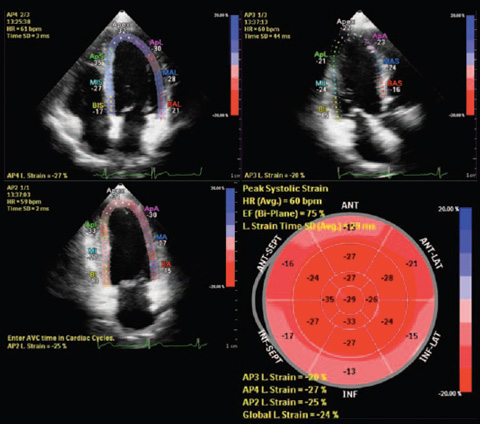

Découvrez HeartModelᴬ⋅ᴵ⋅, une nouvelle application d’intelligence anatomique appliquée à l’échographie (AIUS) intégrant les fonctionnalités suivantes pour l’échocardiographie : quantification 3D temps réel, affichages 2D automatisés et reproductibilité performante. HeartModelᴬ⋅ᴵ⋅ détecte, segmente et quantifie automatiquement l’oreillette gauche et le ventricule gauche à partir d’un volume 3D.

Cette étude a comparé la quantification entre la 2D et HeartModelᴬ⋅ᴵ⋅ 3D temps réel : HeartModelᴬ⋅ᴵ⋅ offre un gain de temps de 82 % lors de l’utilisation de la fonctionnalité d’automatisation et de 63 % lorsque des modifications mineures sont nécessaires.

Une augmentation de la reproductibilité en moins d’étapes et moins de temps que les méthodes classiques peut augmenter la fiabilité du diagnostic pour davantage d’utilisateurs.